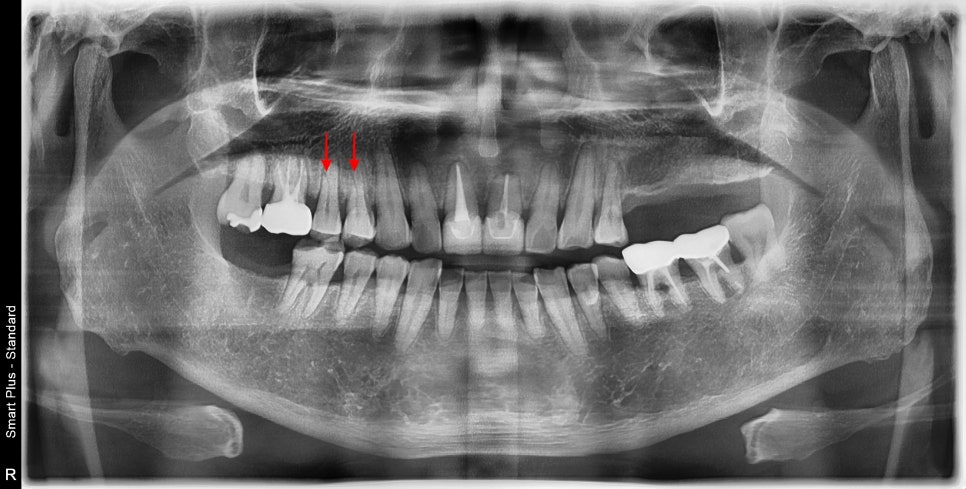

왼쪽 큰 어금니들은 수년 전 발치 상태로 상실되어 있는 상태이고

오른쪽 작은 어금니로 주로 식사를 하고 계셨습니다.

작은 어금니는 저작활동에서 보조적인 기능을 해야 하지만

상기 환자분은 큰 어금니의 상실로 많은 저작력을 받을 수밖에 없었습니다.

화살표를 보면 검은 선이 보이는데 뿌리에 금이 가서 엑스레이상에도 선명히 보였습니다.

자세한 작은 사진에서는 더 선명하게 보였으며

엑스레이에서 치아의 금간부분이 보인다는 것은

발치를 해야 하는 상황까지 왔다는 것입니다.